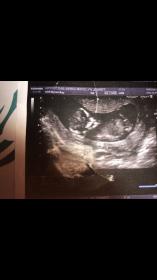

Hi everyone just wondering if you can guess if the skull is girly or boyish? It's too soon for nub theory so hoping someone will guess based on the skill!

Thanks so much xAttachment 35968Attachment 35969

Maybe boy on skull? Not reliable though!